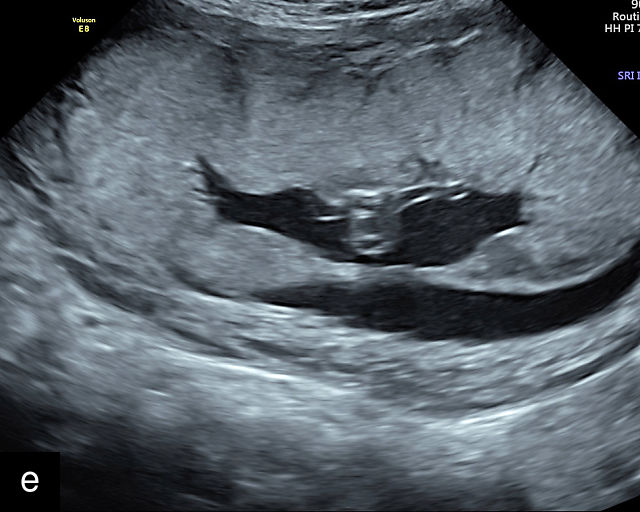

In the early first trimester, trophoblastic tissue appears as an echogenic ring encircling the gestational sac (Figure 1a). By the late first trimester, the placenta becomes recognizable as a distinct structure on ultrasound (Figure 1b). Initially, it presents as a homogeneous echogenic mass (Figure 1b–d) but undergoes progressive differentiation, becoming more heterogeneous as pregnancy advances from the second to third trimester (Figure 1e–g). By the third trimester, cotyledons become discernible, and in the late third trimester, calcifications frequently appear basally and around the cotyledons (Figure 1g).

1

Ultrasound images of development of the placenta (P/p). (a) Trophoblastic tissue appearing as an echogenic ring surrounding the gestational sac at 6 weeks' gestation. (b) Placenta at 12 weeks has become a discrete, uniformly echogenic mass. (c) Placenta at 17 weeks. (d) Placenta at 20 weeks. (e) Placenta at 27 weeks. (f) Placenta at 33 weeks. Increasingly, differentiation and heterogeneous appearance is seen, with demarcation of the cotyledons. Basal calcifications are beginning to appear. (g) Placenta at 40 weeks, showing a distinctly heterogeneous appearance, with clear demarcation of the cotyledons and presence of calcifications.